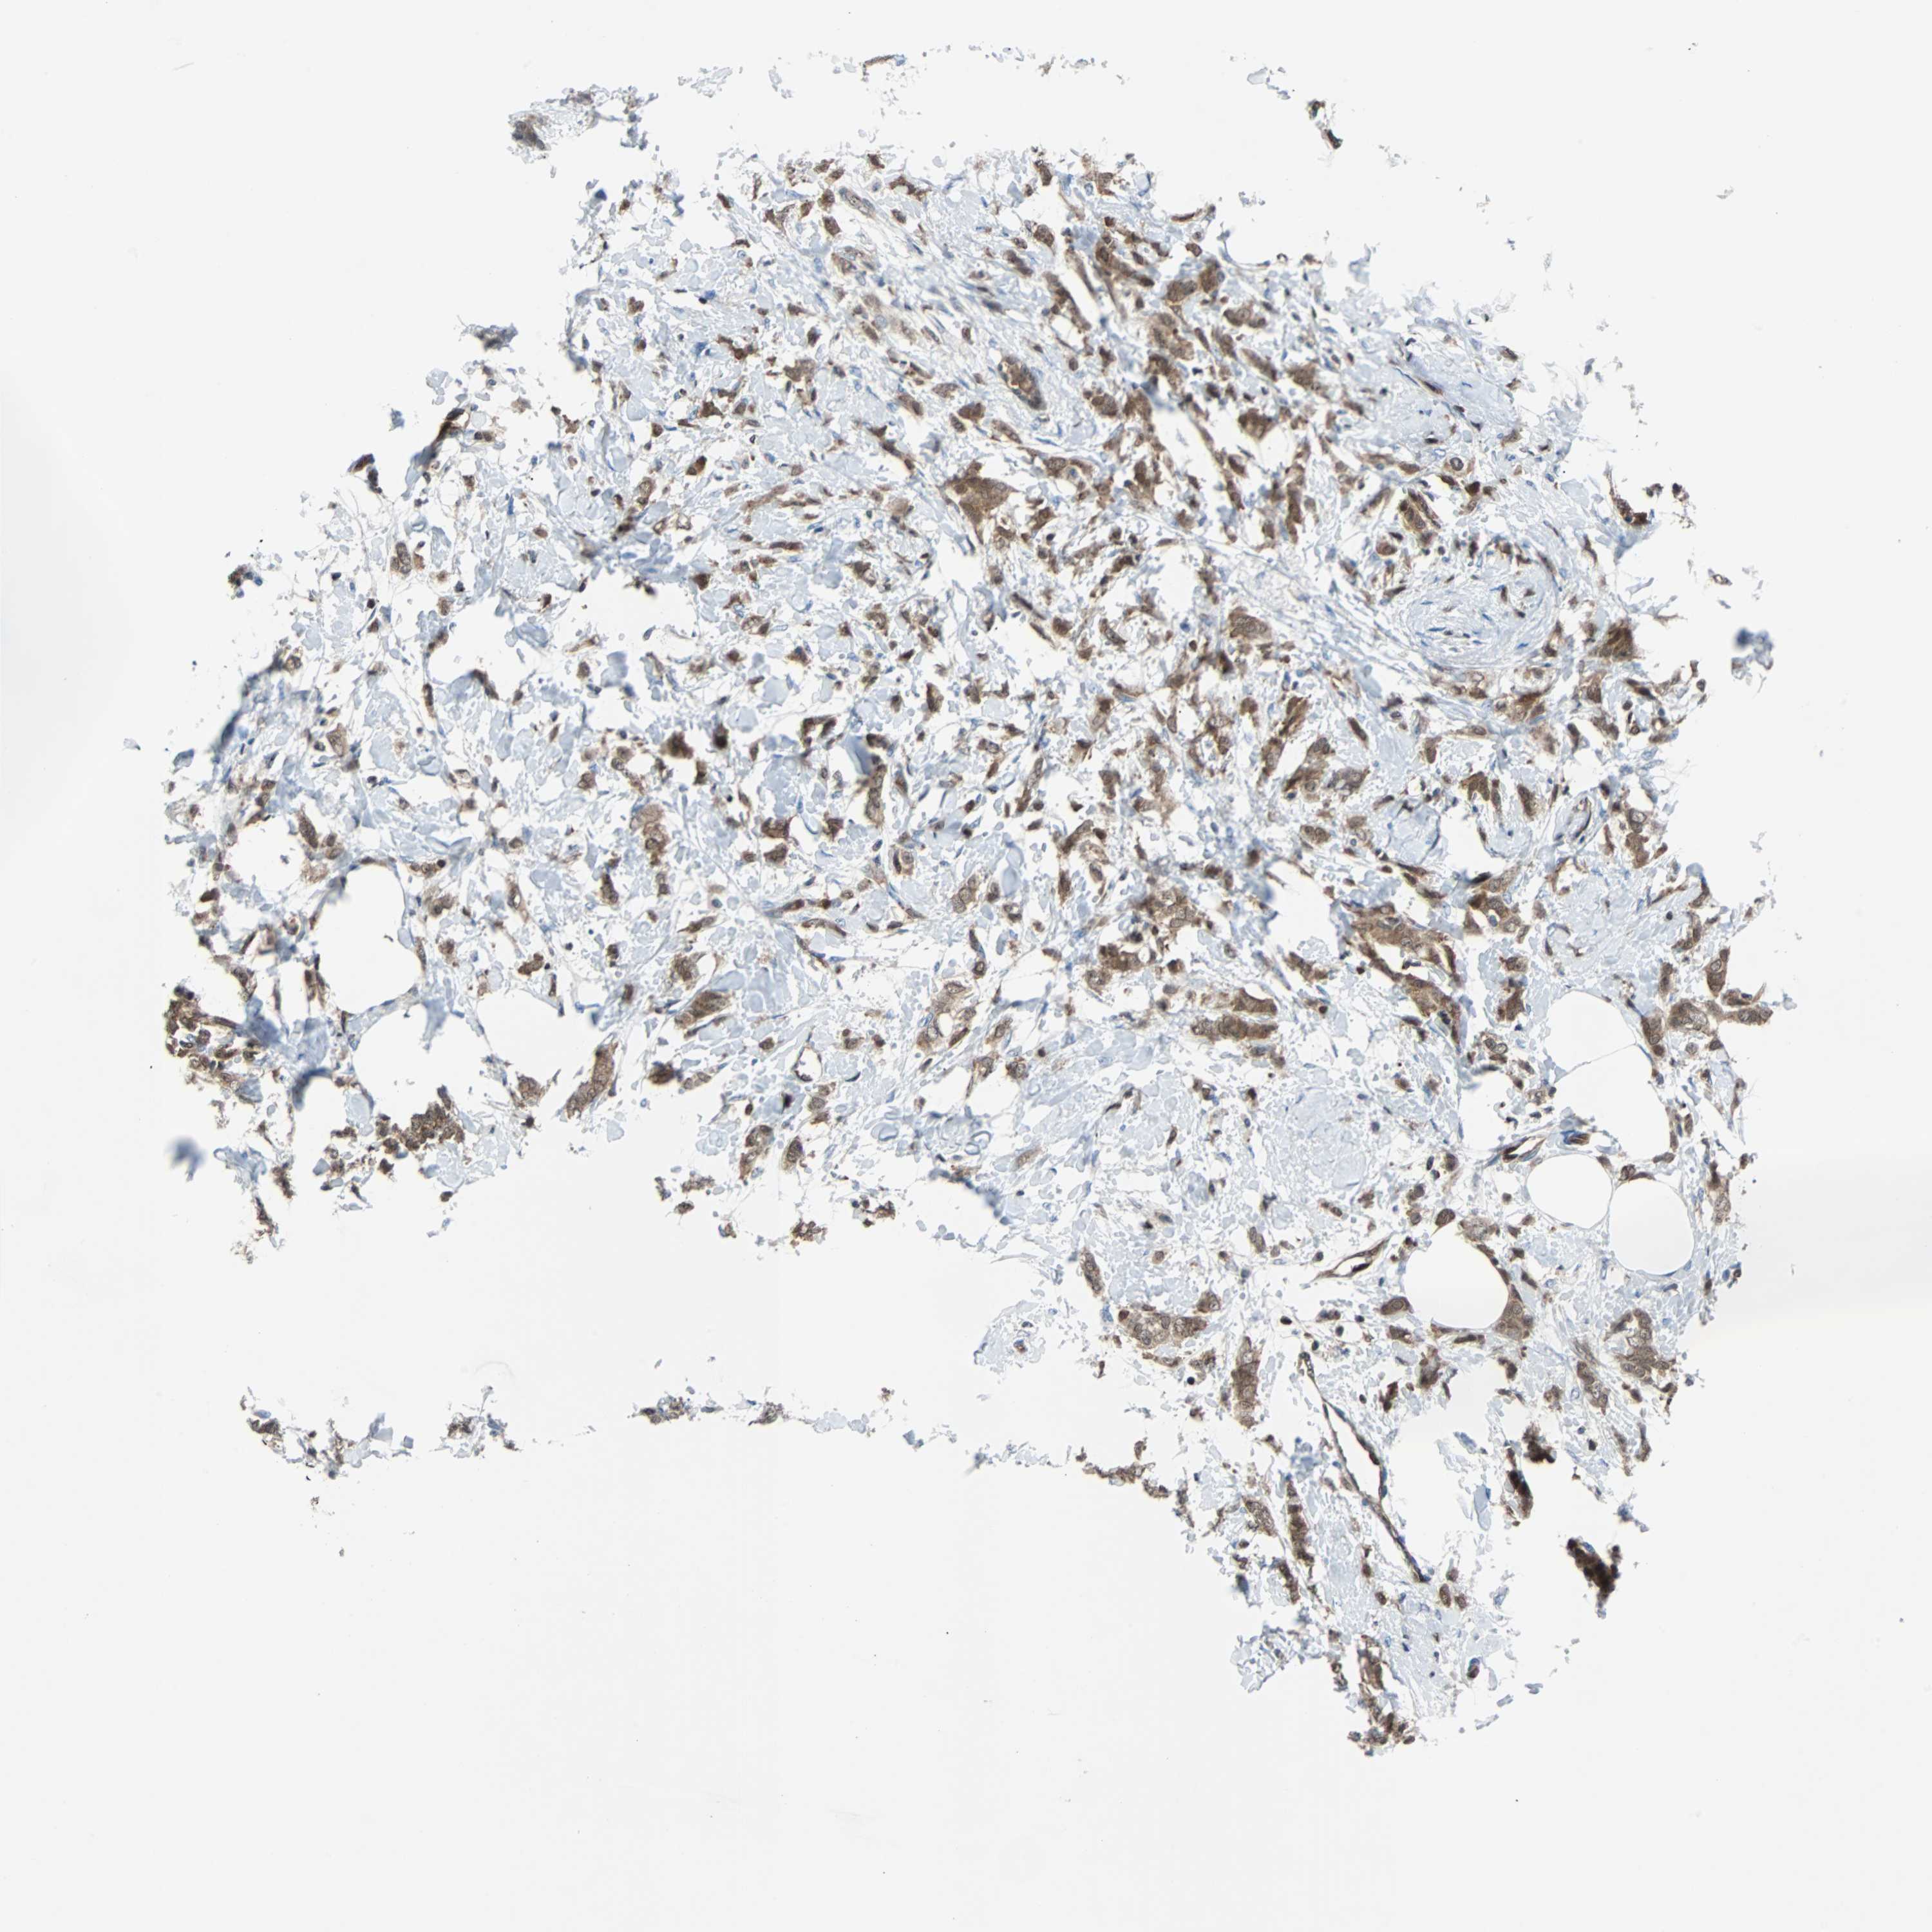

CANCER BREAST CANCER Show tissue menu

BRCA TCGA BRCA VALIDATION PROTEIN EXPRESSION

Breast cancer

Human cancer